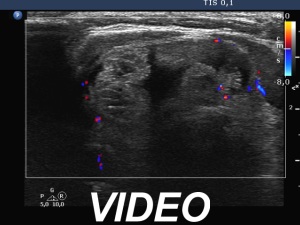

Ultrasonography. The thyroid was echonormal. There was a moderately hypoechoic nodule in the right lobe. The lesion presented halo and both perinodular and intranodular blood flow. The dimensions were 18x11x20 mm, width, depth, length, respectively. The left lobe had a cystic nodule which presented back wall cystic figures but not microcalcifications. The dimensions were 18x16x27 mm, width, depth, length, respectively.

Ultrasonography. Both previously described nodules have significantly increased in size. The dimensions of the right nodule were 25x17x36 mm, width, depth, length, respectively.

The nodule, which was previously described in the left lobe, seemed to be located in the isthmus. The dimensions of this lesion were 36x18x40 mm, width, depth, length, respectively. Except for the significant increase in size, the pattern of the nodules remained unchanged. Several small, hypoechoic discrete lesions were found in the left lobe.Cytology was performed form both nodules and resulted in follicular tumor and benign cystic-colloid goiter, right and left nodule, respectively. The cyst could not be emptied, only a small amount of brown fluid could be aspirated.